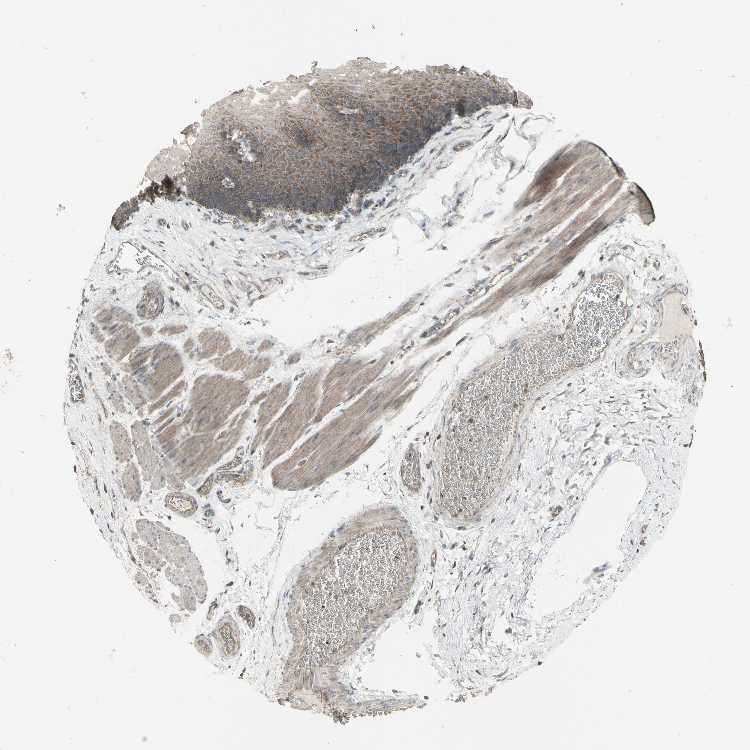

TISSUE PRIMARY DATA ESOPHAGUS Show tissue menu

Esophagus

ESOPHAGUS - Antibody stainingi

Antibody staining in the annotated cell types in the current human tissue is reported as not detected, low, medium, or high, based on conventional immunohistochemistry profiling in selected tissues. This score is based on the combination of the staining intensity and fraction of stained cells.

Each image is clickable and will lead to virtual microscopy that enables deeper exploration of all samples and also displays staining intensity scores, fraction scores and subcellular localization as well as patient and tissue information for each sample.

Antibody HPA001844Antibody CAB005374Antibody CAB016305

Squamous epithelial cells MediumLowHigh